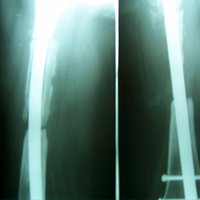

Case:5 Ewing sarcoma with implant failure

Breakage of Nail

Refixation with Angle Bladed Plate and Sever Graft